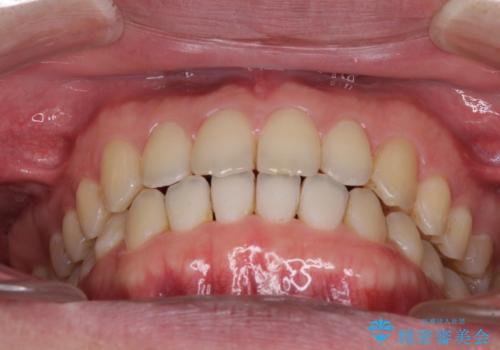

すきっ歯の改善 インビザライン矯正治療

- 上の前歯の隙間を気にして来院された患者様です。

インビザラインにより、上下の歯列を側方に拡大しつつ、前歯の隙間を閉じていくこととしました。

1日22時間の装着時間をしっかりと守ってくださったので、隙間がきれいに閉じ、口元の突出感も改善することができました。